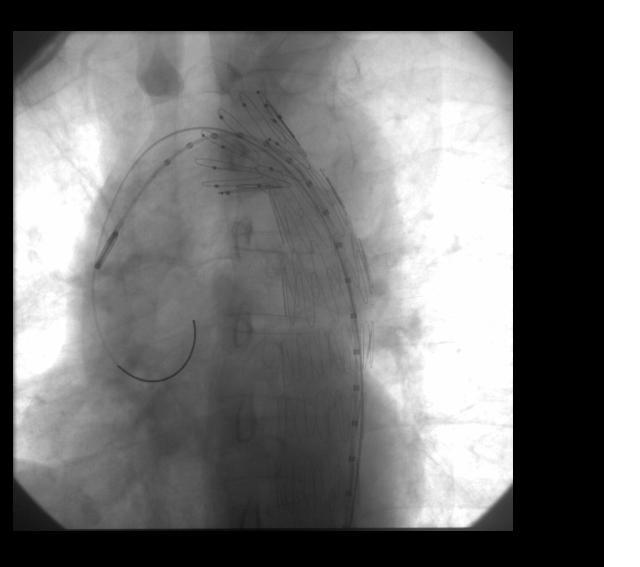

EVAR